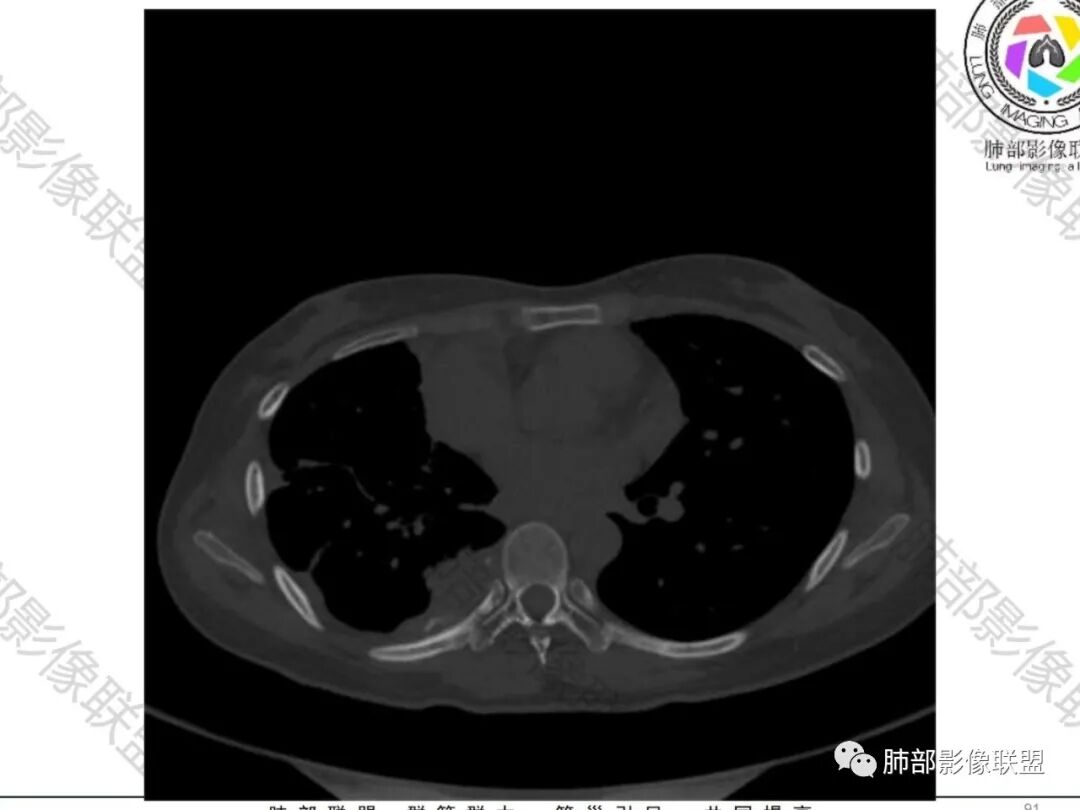

一切∮随缘:双侧胸廓塌陷,以右侧为主,右侧肋间隙狭窄,双肺上叶及右肺下叶胸膜下多发不规则肿块,密度不均匀,内部可见条片状,不规则钙化影,部分钙化不密实,双肺多发纤维索条影,似陈旧性病灶,双侧胸水,临床年轻女性,无感染症状,考虑考虑结核淀粉样变,转移性钙化,弥漫性肺骨化病。

王秀仙:双肺多发条索状及结节状病灶,部分钙化,边界清晰,双侧纵膈胸膜及双侧胸膜可见结块状及弧形软组织肿块,内见多发钙化灶,右侧胸腔塌陷,考虑结核伴淀粉样变性。鉴别胸膜间皮瘤。

丽:双肺散在索条及条片状高密度影,边界清晰,部分实变内可见钙化,支气管管壁增厚,双肺胸膜局限性增厚伴钙化,部分肋骨密度增高,首先考虑结核并淀粉样变性,鉴别转移性钙化,肿瘤样钙质沉着症,胸膜间皮瘤。

傅昌瑜:青年女性,咳嗽胸痛2月,偶有血痰。双肺上叶多发不规则肿块,密度不均匀,内部可见点状、条片状钙化影,右上肺病灶空洞,壁厚薄不均,见壁结节,与支气管关系不清,两侧胸膜增厚,见多发结节,部分结节边缘膨隆明显,结节内亦有多发钙化。上述改变常见于结核、尘肺、钙化性转移等疾病。有膨隆感的结节考虑转移可能性大。

尘缘:青年女性,痰中带血,胸痛2月,无发热盗汗,实验室检查,有贫血,总蛋白降低,血沉情况未知,肿标基本正常。影像表现:双上肺小叶间隔增厚,双侧胸膜广泛不规则增厚,胸膜下多发肿块伴不规则钙化,右侧肋骨破坏。纵隔淋巴结肿大不明显,双肺门淋巴结肿大,部分融合,分析思路:一、感染性病变,1、结核,青年女性,胸膜增厚,多发肿块伴钙化,有咳嗽胸痛,痰中带血,要考虑,但无结核中毒症状,病史仅两月却钙化太明显,肺内没有明显树芽征,存疑,2、其他感染,无炎性指标支持,白细胞不高,可能性小。二、非感染性病变,1、尘肺,胸膜增厚,钙化,胸膜下钙化性肿块,要考虑,但肺内无粉尘结节,无职业史,可能小。2、转移性钙化,无肾脏病史,无血清钙磷代谢异常指标支持,肺内间质无钙沉积改变,基本排除。三、肿瘤性病变,1、肺癌伴转移,双上肺有小叶间隔增厚,双肺门有淋巴结肿大,要考虑,但青年女性,病史两月,钙化太多太广泛,肿标基本正常,可能性小。2、骨肉瘤转移。15-30岁青年人,是骨肉瘤高发年龄,肺内多发成骨样钙化转移灶,双上肺小叶间隔增厚符合癌淋样表现,右侧肋骨破坏,要高度怀疑,需要详细询问病史及手术史。3、软骨来源肿瘤伴肺内转移,右侧肋骨虽有破坏,但无明显软骨样破坏及钙化。可能小。4、其他肿瘤伴转移,青年女性,其他恶性肿瘤能广泛发生钙化性转移的可能性小。综上所述:骨肉瘤伴右侧肋骨及胸膜转移,胸膜下转移,肺内癌淋可能最大,结核不完全除外,下一步需要,仔细询问病史,如果有骨肉瘤史,则基本确诊,如果没有,需要进一步问询呼吸系统症状,病程,以前的影像对照,了解肾脏情况,查血清钙磷指标。

右肺体积缩小,上叶见空洞影

上叶内多个结块,边缘有膨隆,内有钙化灶

钙化灶密度较高,环形/结节状

胸膜及附近肺内见多发结节/斑块

密度类似

边缘膨隆